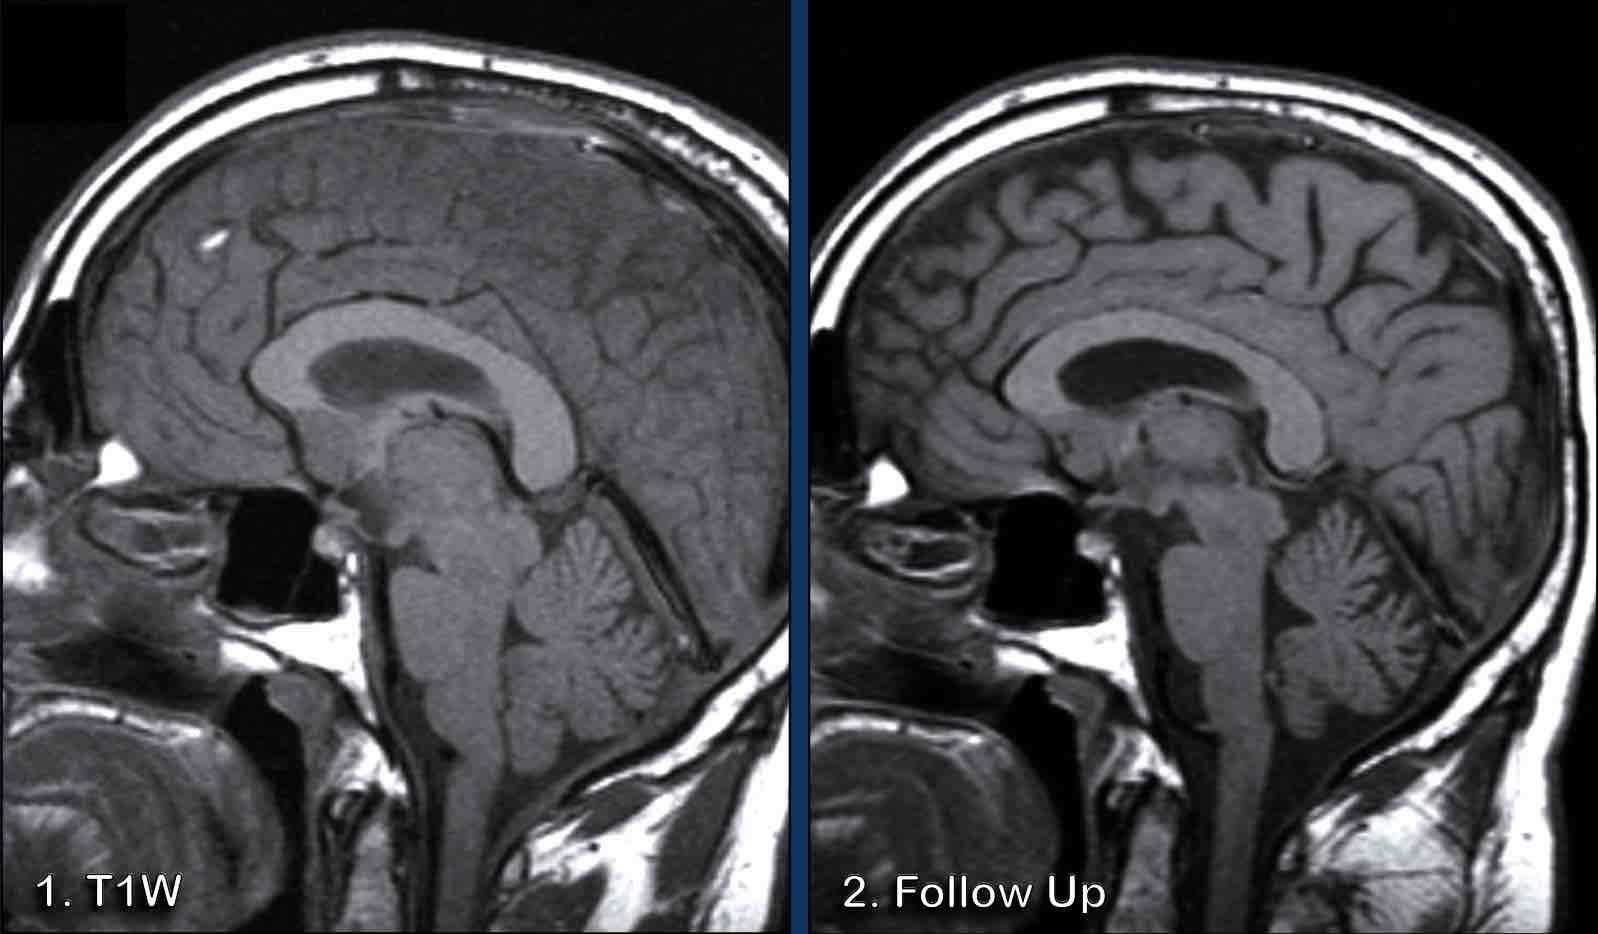

Các hình ảnh này của một bệnh nhân nam 44 tuổi, nhập viện với triệu chứng đau đầu kéo dài, tăng lên khi cúi người về phía trước.

Hình ảnh

Chuỗi xung T2W cho thấy tụ dịch dưới màng cứng hai bên nhỏ (đầu mũi tên).

Sau khi tiêm gadolinium có ngấm thuốc màng cứng đều đặn.

Tiếp tục với các hình ảnh mặt phẳng đứng dọc…

Có sự ứ máu các cấu trúc tĩnh mạch, thể hiện ở xoang dọc trên (đầu mũi tên), xoang thẳng và hợp lưu xoang.

Có sự dịch chuyển xuống dưới của thân não với rút ngắn khoảng cách cầu-vú, dẹt cầu não và gập góc thân não tại chỗ nối sọ-cổ.

Đám rối tĩnh mạch trong khoang ngoài màng cứng phía trước cổ bị giãn rộng.

Kết luận

Các dấu hiệu này điển hình cho hạ áp lực nội sọ.

Bệnh nhân sau đó được chẩn đoán mắc rối loạn mô liên kết.